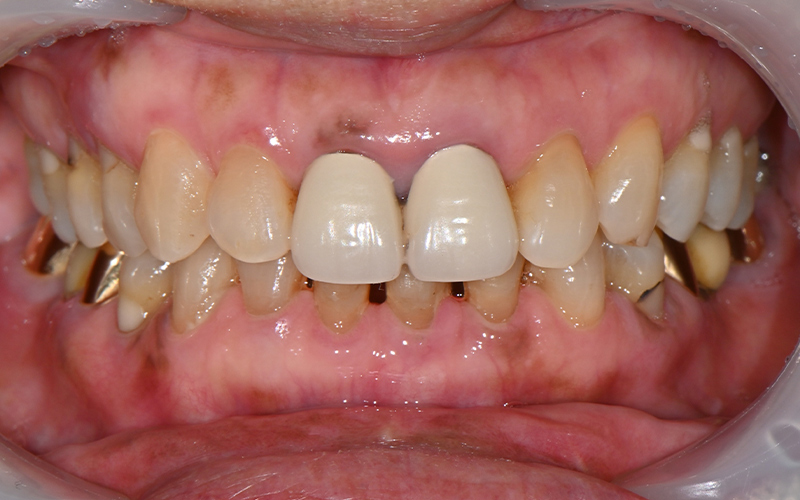

양쪽 어금니가 다 아파서

씹지를 못하겠어요!

오늘 소개해드릴 분은

"양쪽 어금니가 다 아파서

씹지를 못하겠어요"라며

내원하신 70대 여성 환자분이신데요.

일주일 넘게 통증 때문에

식사도 제대로 못하셨다고 합니다.

양쪽 아래 어금니에

통증을 느끼고 계셨고,

파노라마 사진을 촬영해

정밀하게 상황을 체크해보았습니다.